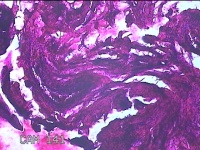

下唇肿物

性别

男

年龄

34岁

临床诊断

唇粘液囊肿

一般病史

下唇肿物2周。

标本名称

大体所见

灰白暗红色肿物0.7x0.5x0.3cm一个,表面光滑。